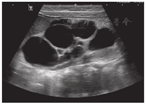

MCDK是婴幼儿肾脏最常见的囊性发育异常性疾病,发病率约为1/3 000[3],是一种非遗传性完全性肾脏发育不良,由于其多囊的超声表现常误诊为多囊肾。因为双侧MCDK患儿不能存活,所以单侧发病多见,患侧肾脏多无功能,同侧输尿管多闭锁或未发育,对侧肾多发育正常,由于对侧健康肾脏代偿性增大,肾功能正常。单侧MCDK患者,临床多无特异性症状和体征,预后良好,一般也不发生癌变,可手术切除[4,5];如果对侧肾脏发育异常,如常合并肾盂输尿管连接部梗阻、重复肾、膀胱输尿管反流等[6],预后则取决对侧肾脏的异常严重程度,如同时伴肾外畸形,则预后不良。MCDK典型的超声影像学特点是患侧肾脏失去正常形态,由数量不等、大小不一的多个薄壁囊肿组成,各囊肿互不相通,囊肿间由于结缔组织增生看不到肾实质或仅有少部分肾实质(图1)。同侧输尿管多不显示。同时要仔细观察对侧肾脏是否发育正常,有助于评估预后。大多数患儿在产前超声检查时发现,出生后的患儿需要超声密切随访观察肾脏发育状况[7],该病可随时间推移而发生退化,最终演变为小瘤样组织。当患儿出现血压增高或患侧肾脏合并巨大囊肿时需手术切除,因此,对MCDK囊肿大小的评估至关重要。本病与重度肾积水不同,一般情况下,重度肾积水内的多个液性囊腔是由明显扩张的肾盂肾盏形成的,彼此连通,囊腔间可见菲薄的肾实质,探查肾盂输尿管连接部具有重要的诊断意义[8]。